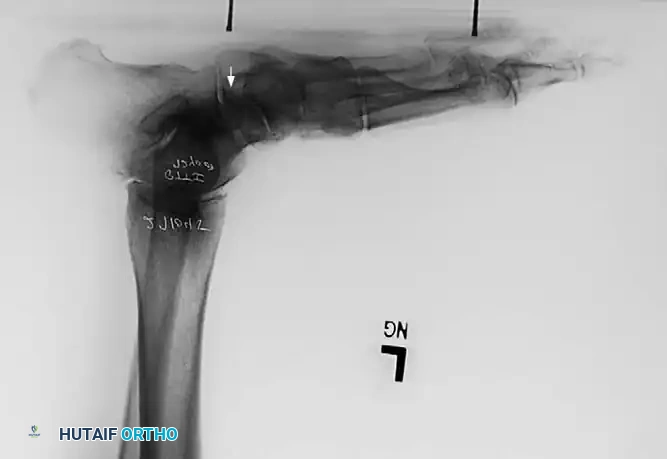

Associated Surgical & Radiographic Imaging